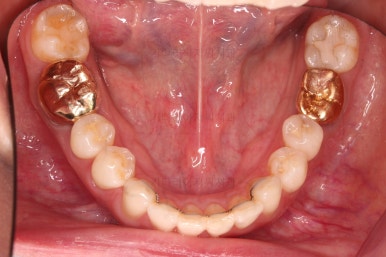

아랫니 부분교정이 끝났고요.

어금니도 원위치로 많이 갔네요.

아랫니 부분교정과 어금니 부분교정은 비교적 조기에 끝났으나(7개월) 임플란트가 생각보다 오래 걸렸습니다.

치료 종료시의 모습인데요.

임플란트가 잘 들어갔고 아래 앞니도 원하는 모습으로 잘 배열이 되었습니다.